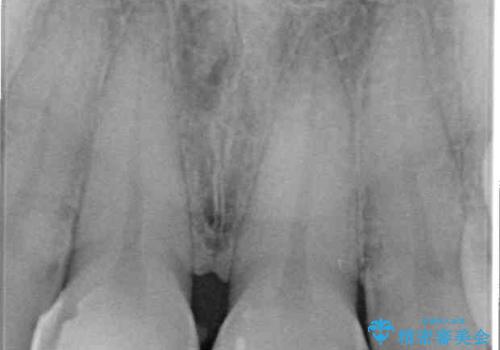

- 上の前歯2本の審美障害を気にして来院された患者様です。樹脂が無造作に充填されており、色合いも形態も不自然で、歯肉も腫れているため、オールセラミッククラウンにて補綴することとしました。

充填されたレジンを取り除いたところ、歯肉の炎症による出血が認められました。セラミッククラウン装着後は歯肉が腫れることもなく、仕上がりも自然な歯のようになり、患者様には大変満足していただきました。